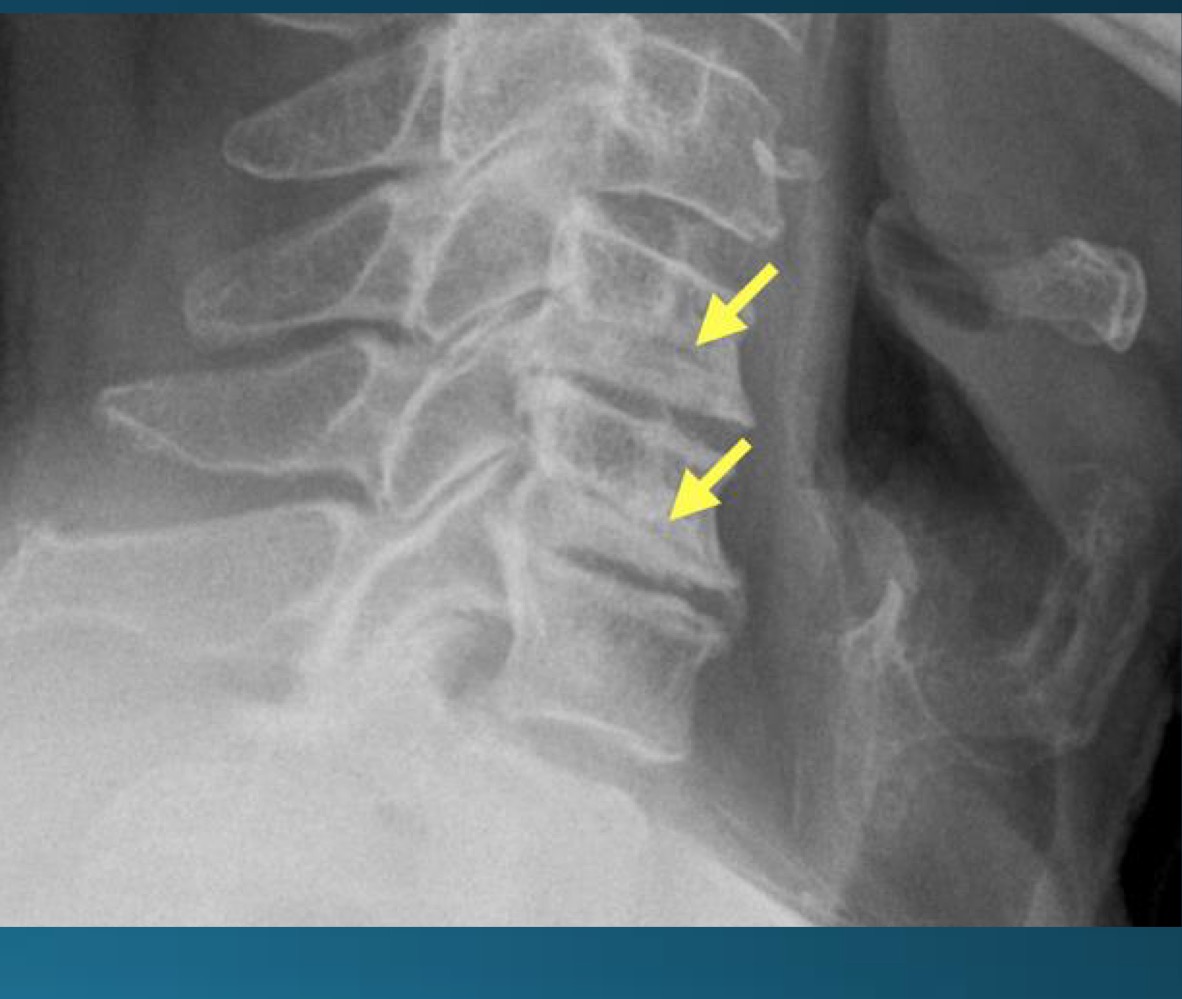

what are the findings in this image?

uncovertebral joint arthrosis

what do you call the radiographic feature commonly seen in uncovertebral joint arthrosis

pseudofracture